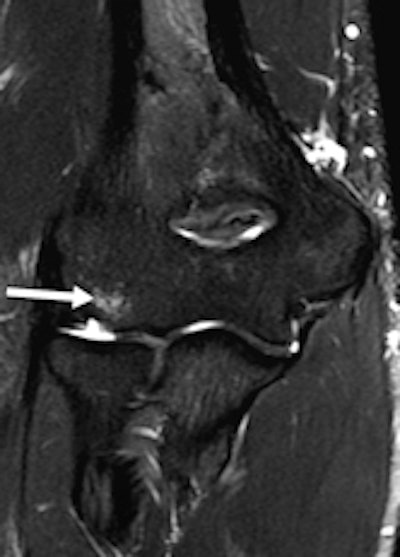

A 20-year-old male weightlifter with flare-up of chronic elbow pain. Coronal proton density-weighted fat-saturated MRI (left) and coronal proton density-weighted nonfat-saturated MRI (right) show anterior bundle UCL midsubstance tear (arrows). Absence of significant edema within disrupted fibers and adjacent soft tissue suggests that tear is chronic.

A 20-year-old male weightlifter with flare-up of chronic elbow pain. Coronal proton density-weighted fat-saturated MRI (left) and coronal proton density-weighted nonfat-saturated MRI (right) show anterior bundle UCL midsubstance tear (arrows). Absence of significant edema within disrupted fibers and adjacent soft tissue suggests that tear is chronic.Of the 28 athletes, 15 were male and 13 female, and the mean age was 25 years (standard deviation 5.2 years), according to Bethapudi, whose co-authors came from the International Olympic Committee in Lausanne, Switzerland, and the department of orthopedic surgery at Oslo University.